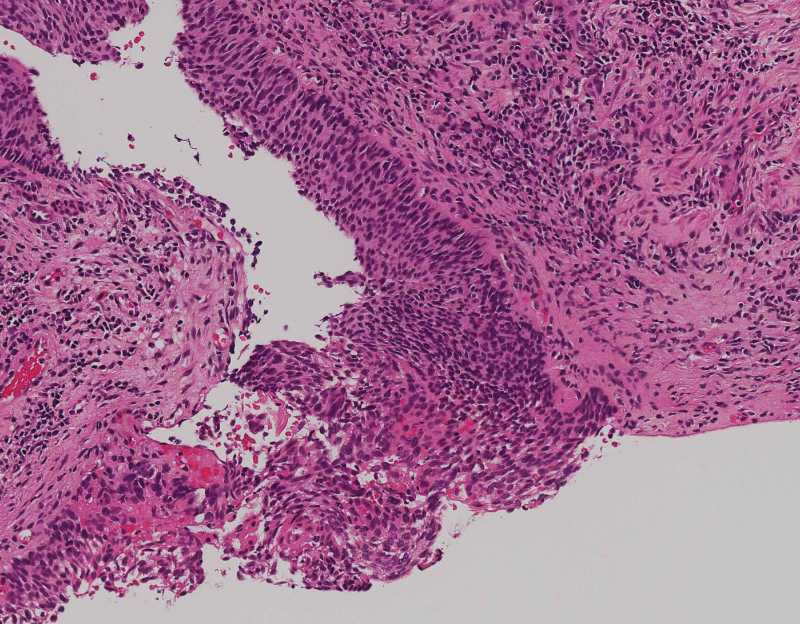

性别

女

年龄

57

临床诊断

宫颈高级别鳞状上皮内病变

一般病史

HPV16阳性,TCT:HSIL

标本名称

宫颈活检

大体所见

灰白组织两块,共大0.5X0.5✕0.4CM。

请老师指教一下,这种可以下到浸润了吗?

鳞癌

考虑:鳞癌伴有浸润。建议:P16;P53;Ki67等。